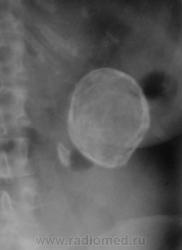

Больше данных за обызествленную кисту неясного генеза.

Обезыствленная полость в почке в сочетании с нефросклерозом. Помимо эхинококка нельзя исключить и обезыствленную туб. каверну. Туберкулез тоже, как известно, любит кальций.

Вполне м.б. закрытой эхинококковой кистой почки (или не почки) в сочетании с камнем. Возможно, у меня богатая фантазия, но, что за тень бобовидной формы слева на уровне Th12 - L1? Из опыта знаю, результаты УЗИ иногда лучше не принимать во внимание.

По снимку данное образование находится в проекции почки , правая-то хорошо визуализируется. А слева?

Вот только, как мне кажется , и по размеру разногласия, описывается образование 5 см, но на снимке кажется больше .

Интересно, а что, это, рядом с такой "каменюкой", маленькая "каменючка"?

"Младший братик" в синусе почки!

Тогда, выходит допустимо, предположить, что "булыжник" в почке, в лоханке?

Ребра тоже с известью... Склонность к кальцинозу. А не эхинококк? Протокол УЗи вызывает огромное сомнение в квалификации врача...

Один из коллег, ранее, высказал предположение, что имеет место, быть эхинококк селезенки.